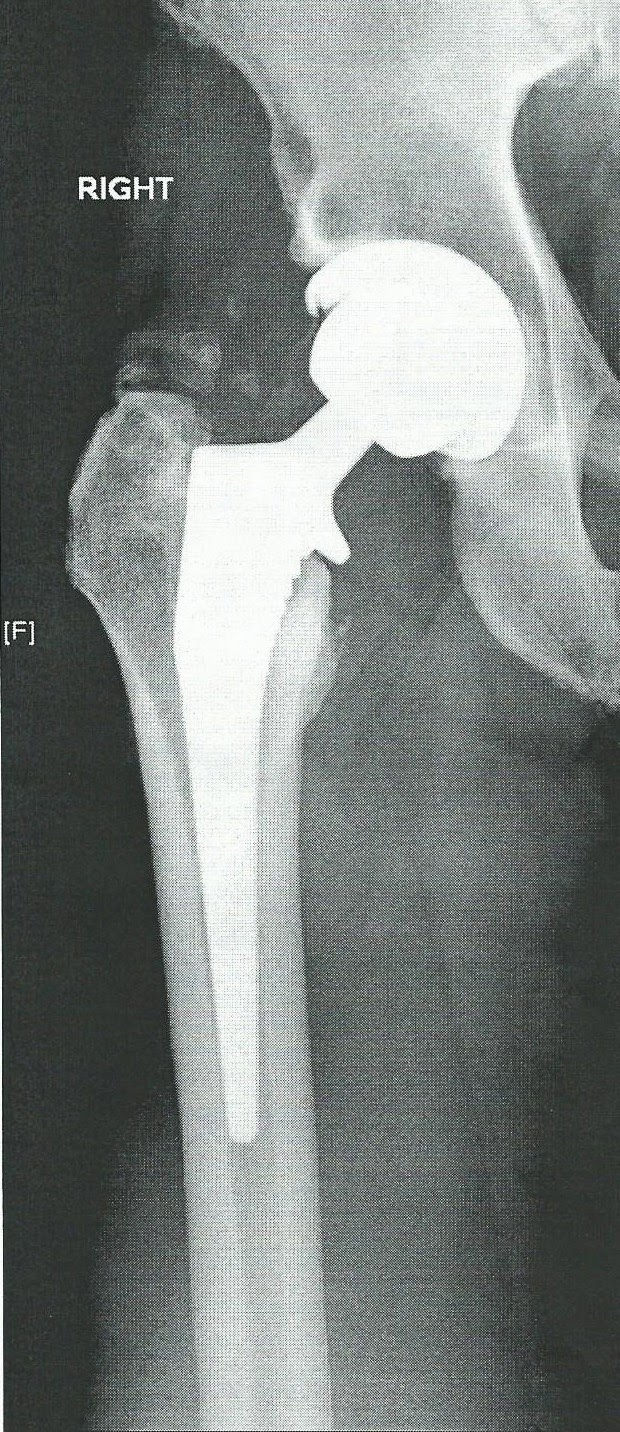

from photonsandelectrons.blogspot.com

Photons and Electrons My Minimally Invasive Total Hip Replacement With